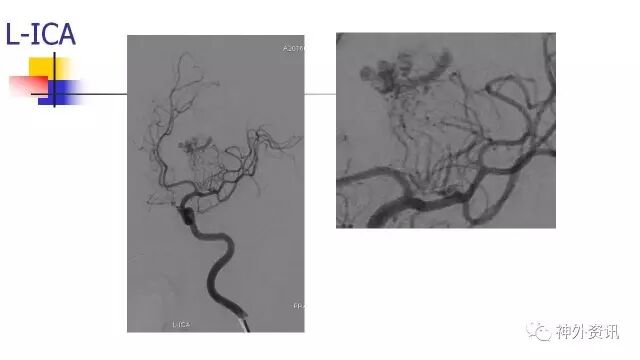

L-ICA动态